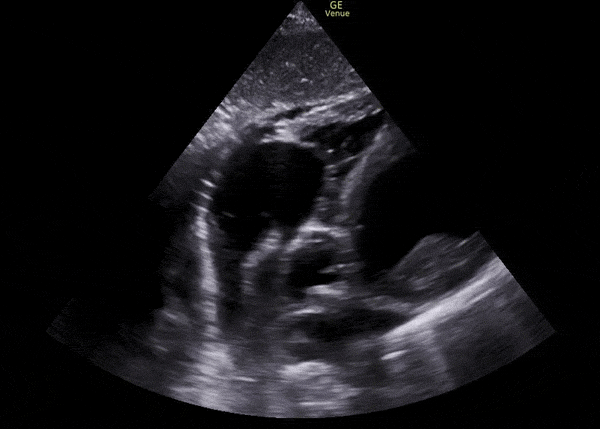

Left Ventricle Thrombus

The following three images show a clot in the left ventricle. Notice that it adheres to the ventricular wall. Such clots are called mural thrombi. They form within the ventricle itself as opposed to having formed elsewhere and embolized. They are the result of disruptions to laminar blood flow through the heart. Common causes include dilated cardiomyopthies, post ischemic regional wall motion abnormalities, atrial fibrillation, or very low ejection fractions. As the left side of the heart is emptied by the aorta, left ventricular thrombi pose a risk for peripheral arterial occlusions – specifically embolic strokes. However, if the clot embolized through the aorta but did not make it up the carotids, other peripheral infractions could certainly arise as well.

Of note, a right sided clot could get to the left ventricle if there were a ventricular septal defect or other communication between the two sides. However, that would not cause a mural thrombus, as we see here.